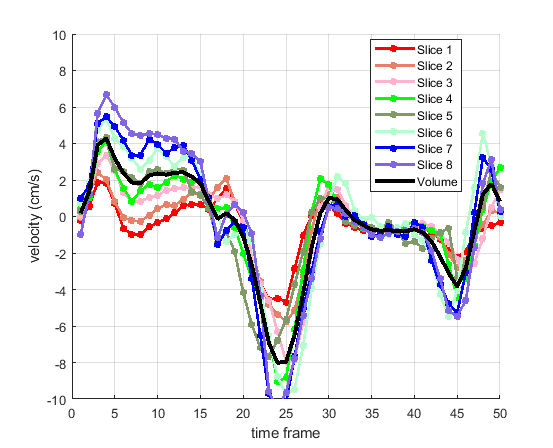

Time courses of the estimated translational component per subject, frame, slice and volume along the 3 velocity directions x, y and z are presented in Fig.6 - Fig.8.